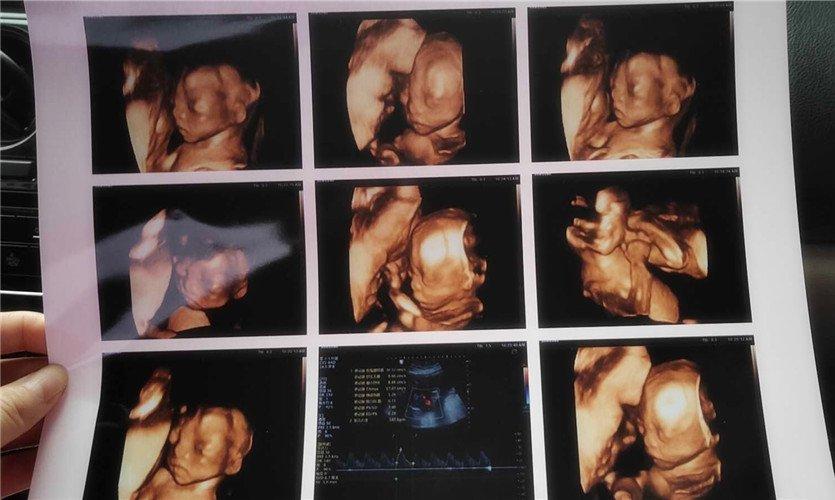

四維彩超是一種先進的醫學影像技術,通過實時觀察胎兒在母體內的活動情況,為醫生提供了豐富的診斷信息,在四維彩超下,我們可以清晰地觀察到胎兒的蛋蛋(睪丸)的形態、位置和大小等特征,胎兒蛋蛋是男性生殖系統的重要組成部分,對于胎兒的生長發育具有重要意義。

四維彩超下胎兒蛋蛋的樣子

在四維彩超下,胎兒蛋蛋呈現出特定的形態和外觀,通常情況下,胎兒蛋蛋呈現出圓形或橢圓形,表面光滑,內部回聲均勻,隨著胎兒的發育,蛋蛋會逐漸增大,并呈現出明顯的性別特征,醫生可以通過四維彩超技術,對胎兒蛋蛋的大小、形態和位置進行評估,以判斷胎兒生殖系統的健康狀況。

胎兒蛋蛋的發育是一個復雜的過程,受到多種因素的影響,在胎兒發育的早期階段,蛋蛋位于腹腔內,隨著胎兒的生長發育,蛋蛋逐漸下降至陰囊,這個過程受到激素、遺傳和環境等多種因素的影響,在四維彩超的觀測下,我們可以實時了解胎兒蛋蛋的發育過程,及時發現異常情況并采取相應的治療措施。